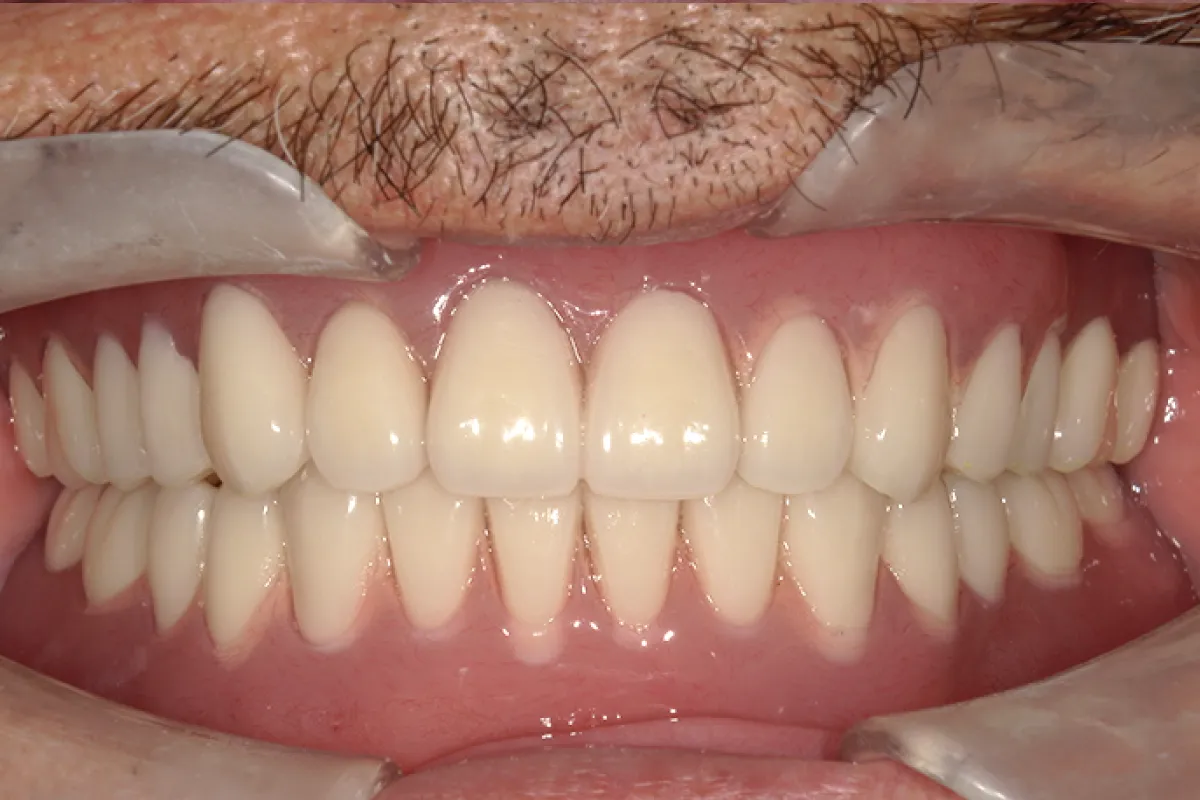

患者様のお悩み 歯牙動揺による咀嚼障害 (欠損や動揺歯が多く噛めない、入れ歯で痛みが出る) 治療概要 インプラント・オールオン4・抜歯・ジルコニア 前歯を含めた複数の部位で歯牙の自然脱落があり、どうにかした […]